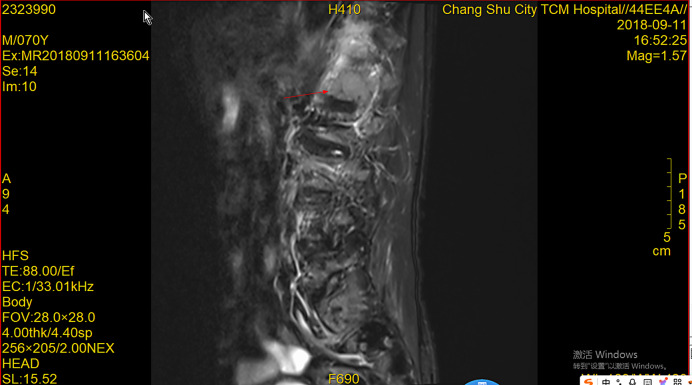

前列腺癌是男性最常见的恶性肿瘤之一,骨转移是常见的并发症,严重影响患者的生活质量和生存率。病例介绍:本文报道一例前列腺癌多发骨转移患者在化疗联合内分泌治疗后完全缓解并存活6年。结论:本文通过详细介绍患者的治疗过程及随访结果,探讨化疗联合内分泌治疗在前列腺癌骨转移治疗中的应用价值。

Case presentation: This article reports a case of a patient with multiple bone metastases from prostate cancer who achieved complete remission and survived for 6 years following chemotherapy combined with endocrine therapy.